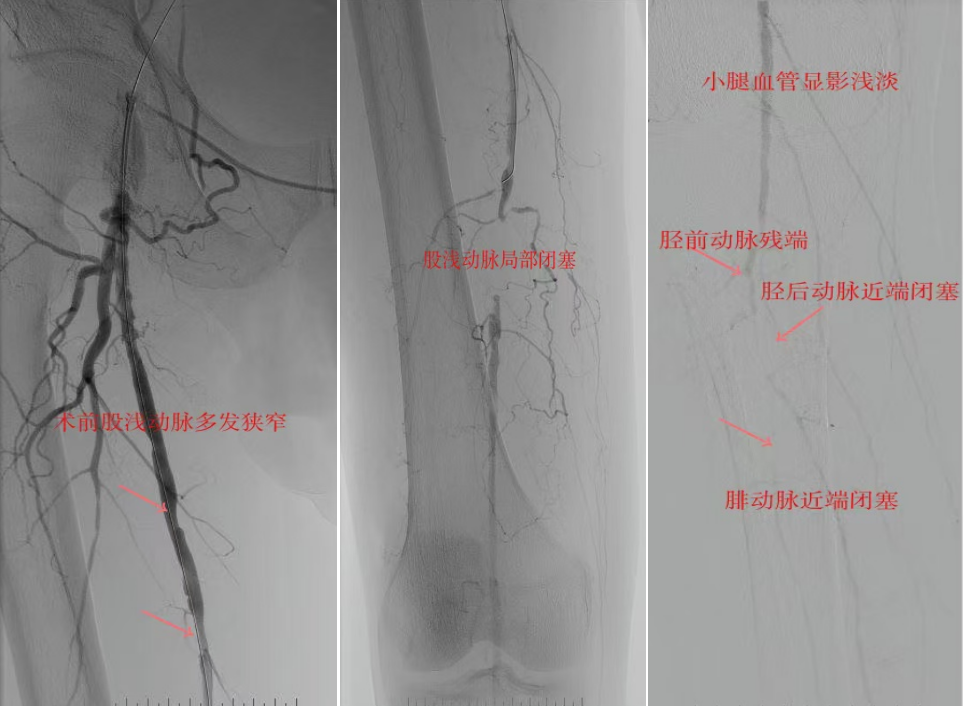

78歲男性患者,糖尿病合并高血壓、腦梗塞,右足持續(xù)疼痛伴冰涼發(fā)紺3個(gè)月。入院CTA顯示其右側(cè)股淺動(dòng)脈全程閉塞,膝下三支動(dòng)脈均閉塞。醫(yī)療團(tuán)隊(duì)在局部麻醉下,再次巧妙應(yīng)用“逆向開(kāi)通技術(shù)”,經(jīng)脛后動(dòng)脈——足底弓逆向開(kāi)通足背動(dòng)脈及脛前動(dòng)脈。術(shù)后患者右足皮溫即刻回升,疼痛消失。術(shù)后結(jié)合中藥外治(換藥、熏洗、去腐生肌膏外敷)加速創(chuàng)面愈合,患者已順利出院。

影像檢查:CTA顯示右側(cè)股淺動(dòng)脈全程閉塞,膝下三支動(dòng)脈(脛前、脛后、腓動(dòng)脈)完全閉塞。

兩例患者共同凸顯三大高難度治療挑戰(zhàn):1.患者高齡且基礎(chǔ)病復(fù)雜;2.血管全程多節(jié)段閉塞、鈣化程度嚴(yán)重;3.常規(guī)順向開(kāi)通路徑已被完全阻斷。團(tuán)隊(duì)果斷采用遠(yuǎn)端逆行穿刺技術(shù),在纖細(xì)的足踝部血管建立治療通道,實(shí)現(xiàn)“逆向破冰”。